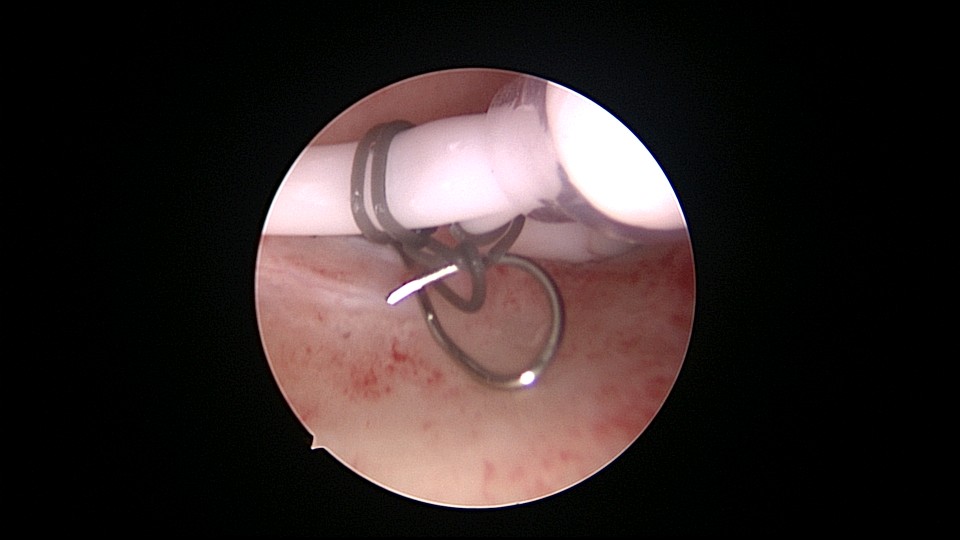

患者53岁,G3P1,顺产1次(产后大出血)。1年前因盆腔器官脱垂行阴道前后壁修补手术,同时行宫腔镜息肉切除手术,病检为增生反应子宫内膜伴出血。2025年2月,绝经2年,阴道出血半天,行宫腔镜检查及诊刮,放置曼月乐并固定,用曼月乐尾丝连接环与不锈钢挂钩,将挂钩插入宫底肌层固定,异物钳原位固定曼月乐,退出宫腔镜,结束手术。2025年4月复查B超曼月乐位置正常,环顶端距宫底1.1cm。病检为子宫内膜增生,不伴非典型增生。